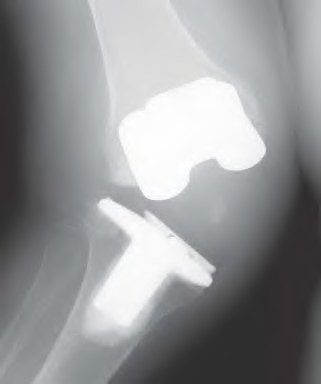

Figure A demonstrates a total knee prosthesis design. Which of the following motions is constrained in this particular design:

1) Complete anterior-posterior translation constraint only

2) Partial varus-valgus angulation constraint only

3) Partial varus-valgus angulation and partial internal-external rotation constraint

4) Complete internal-external rotation constraint only

5) Complete varus-valgus angulation and anterior-posterior translation constraint

Figure A demonstrates a non-linked, constrained total knee arthroplasty prosthesis. This drawing depicts the degree of coronal plane and rotational constraint provided by the tall, wide tibial spine in the deep femoral box. This design constrains varus-valgus (allows 2°-3°) and internal-external rotation (allows 2°). A linked, rotating-hinge prosthesis (Illustration A) constrains anterior-posterior translation in addition to varus-valgus and internal-external rotation.

The article by Scuderi reports that in revision TKA, the goal is to restore the original anatomy, restore function, and provide a stable joint. To this point of stability, it is preferable to implant the prosthesis that provides adequate stability with the least mechanical constraint possible to avoid bone-implant stresses that may cause early loosening. Therefore, it is preferable to use a posterior-stabilized (cruciate substituting) articulation (Illustration B) if the knee remains stable without constrained components.

McAuley et al suggest that more predictable results are obtained with the use of cruciate-substituting components. However, if there is functional loss of the medial collateral ligament or lateral collateral ligament, inability to balance the flexion and extension spaces, or a severe valgus deformity, then a constrained

condylar prosthesis is needed.

Rodriguez et al reports Level 4 evidence of 44 patients revised with varus-valgus constrained implants followed for an average of 5.5 years. There was a theoretical concern that the increased constraint of the prosthesis would lead to component loosening, however their series had only one femoral component and no tibial components that loosened.